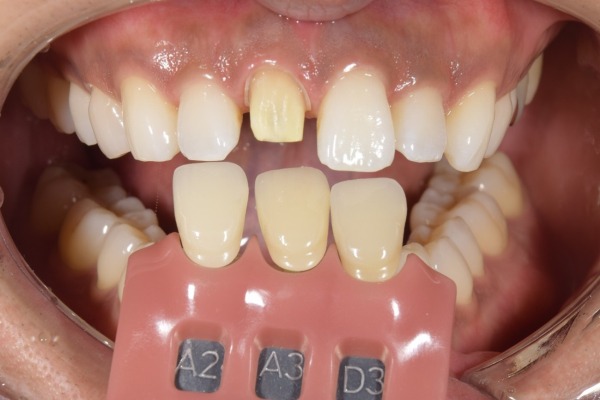

開口時の写真です。

色合わせをしている口腔写真です。